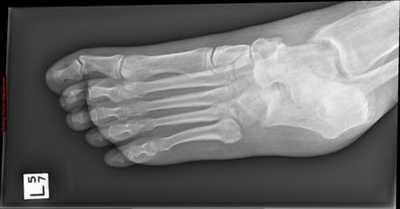

Пациент М. 1980 г.р., травму получил при падении на стопы с высоты 1,5 метра. Лечился по месту жительства (в травмпункте районной больницы) консервативно в гипсовой повязке в течение 14 дней. Консультирован в травматологическом отделении ФГБУ «УНИИТО им. В.Д. Чаклина» Минздрава РФ, предложено оперативное лечение. При поступлении кожные покровы стопы чистые, без признаков воспаления и сдавления тканей. Стопа отечна, уплощена. На рис. 1 представлены рентгенограммы пациента. Прооперирован через 2 недели после травмы. Операция состоит из двух этапов. Первый этап заключается в наложении дистракционного аппарата. Проводятся две спицы 1,8 мм во фронтальной плоскости: первая через нижнюю треть диафиза большеберцовой кости, вторая через бугор пяточной кости (рис. 2). Спицы фиксируются в дистракционном аппарате, выполненном из двух полуколец, соединенных между собой двумя телескопическими тягами. Особое расположение полуколец, фиксация спиц на концах полуколец, крепление кронштейнов для телескопических тяг обеспечивает тракцию пяточной кости в необходимом направлении с использованием минимального количества спиц и внешних опор при сохранении необходимого поля обзора для проведения рентгенологического и визуального контроля репозиции и фиксации. Второй этап - закрытая элевация импрессированной суставной поверхности и окончательная репозиция пяточной кости. Через разрез длиной до 1 см по латеральному краю ахиллова сухожилия (рис. 3) в месте его прикрепления к пяточной кости под соответствующий фрагмент подводится элеватор (рис. 4), манипуляцией которым устраняется смещение и выполняется провизорная фиксация спицами 1,5 мм (рис. 5). При сагиттальном раскалывании суставной фасетки целесообразно проведение одного-двух винтов субхондрально (рис. 6). Стержень вводится с дорзальной поверхности пяточной кости по ее оси через разрез до 2 см по предварительно сформированному остеотомом каналу (рис. 7, 8). Далее через проколы кожи с помощью кондуктора (рис. 9) выполняется запирание винтами с латеральной поверхности, внешнее устройство демонтируется. Достигнуто удовлетворительное стояние отломков (рис. 10).

Рис. 1. На рентгенограмме левой стопы в прямой и боковой проекциях определяется оскольчатый внутрисуставной перелом левой пяточной кости

Рис. 10. На рентгенограмме левой стопы в прямой и боковой проекциях определяется удовлетворительное стояние костных фрагментов на фоне металлофиксатора